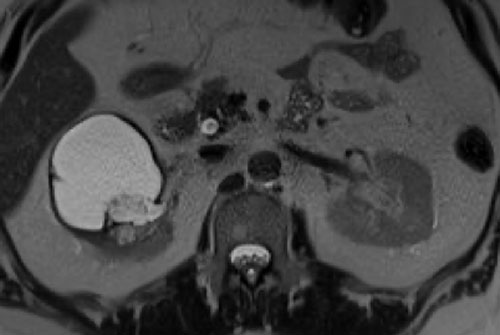

Có một khối dạng nang ở thận phải với nhiều (> 4) vách ngăn mỏng, nhẵn, có ngấm thuốc.

Tổn thương được phân loại là Bosniak IIF.